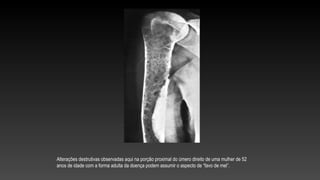

Alterações destrutivas observadas aqui na porção proximal do úmero direito de uma mulher de 52

anos de idade com a forma adulta da doença podem assumir o aspecto de “favo de mel”.